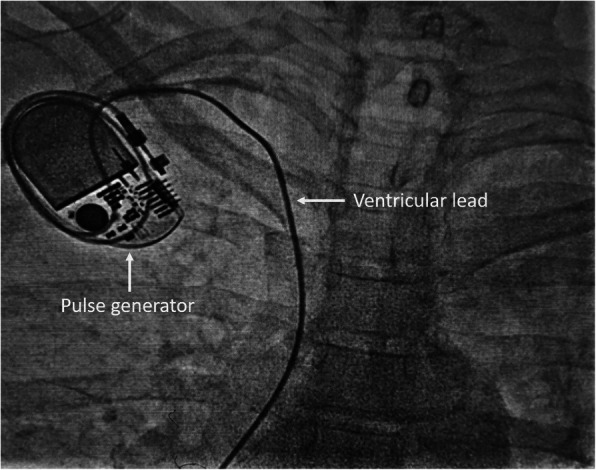

A temporary pacemaker was inserted through the right femoral venous route and she was subsequently planned for permanent single-chamber pacemaker implantation. A Dual-chamber pacemaker, although ideal, was refused by the patient due to financial reasons. As part of the hospital protocol, an intravenous contrast (iohexol; 5 ml diluted in 5 ml normal saline) injection was given through the left brachial vein to delineate the venous anatomy and drainage of left upper limb veins, which showed good-sized axillary and subclavian veins draining into the left brachiocephalic vein and then into superior vena cava (Fig. 1). We made the skin incision in the left infraclavicular fossa and prepared the subcutaneous pocket for device placement. Then, we proceeded to an axillary venous puncture with 16 G needle using the Seldinger technique. However, the axillary vein could not be cannulated despite multiple attempts. To find out the cause, we gave another contrast injection in the left brachial vein which revealed severe spasm of axillary and subclavian veins (Fig. 2). Then, axillary vein puncture was attempted after 15 min of giving two sequential boluses of intravenous nitroglycerin (200 mcg followed by 400 mcg) with a gap of 5 min, still, the axillary vein could not be cannulated. A venogram was not done on the right side to avoid the risk of venous spasm and the axillary vein was cannulated using anatomical landmarks, and the pacemaker was successfully implanted in the right infraclavicular pocket (Fig. 3). Active fixation lead was screwed in right ventricular septum and the device was placed in a right infraclavicular pocket; the VVIR mode for pacing was selected. Skin incisions on both sides of the chest were closed in layers.

Fig. 3.

Final implantation of single-chamber permanent pacemaker from the right side